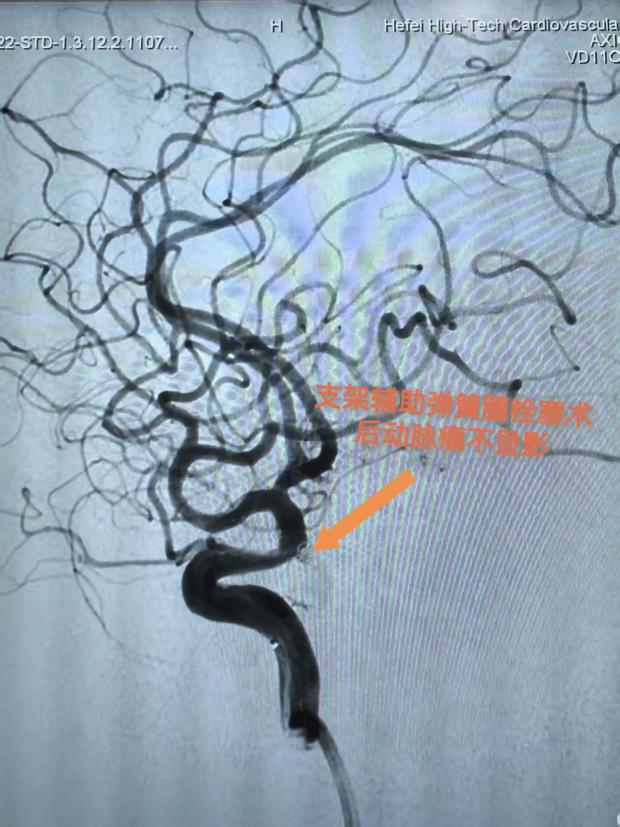

经过神经外科团队讨论,为王女士制定了支架辅助弹簧圈栓塞术方案。该方案的核心原理是,首先在动脉瘤的开口处(即瘤颈)植入一枚支架,这枚支架如同“栅栏”一般,既能有效阻挡后续填入的弹簧圈脱落至正常血管,又能通过改变动脉瘤区域的血流方向,促进瘤腔内血栓的形成;随后,通过微导管将柔软的铂金弹簧圈精准送入动脉瘤腔内,逐步填充并闭塞瘤腔,从而从根本上消除动脉瘤破裂的风险。术后造影显示动脉瘤100%栓塞,支架通畅,无血管痉挛或出血,手术顺利结束。

王女士的案例证明,即使是高龄、合并多种基础病的宽颈颅内动脉瘤患者,通过支架辅助弹簧圈栓塞术这一微创技术,也能安全有效地“拆除”脑血管里的“定时炸弹”。关键在于:早诊断、选对术式、严格围手术期管理及长期随访。控制好血压、规律服药、健康生活方式,才能让大脑“血管长城”固若金汤!